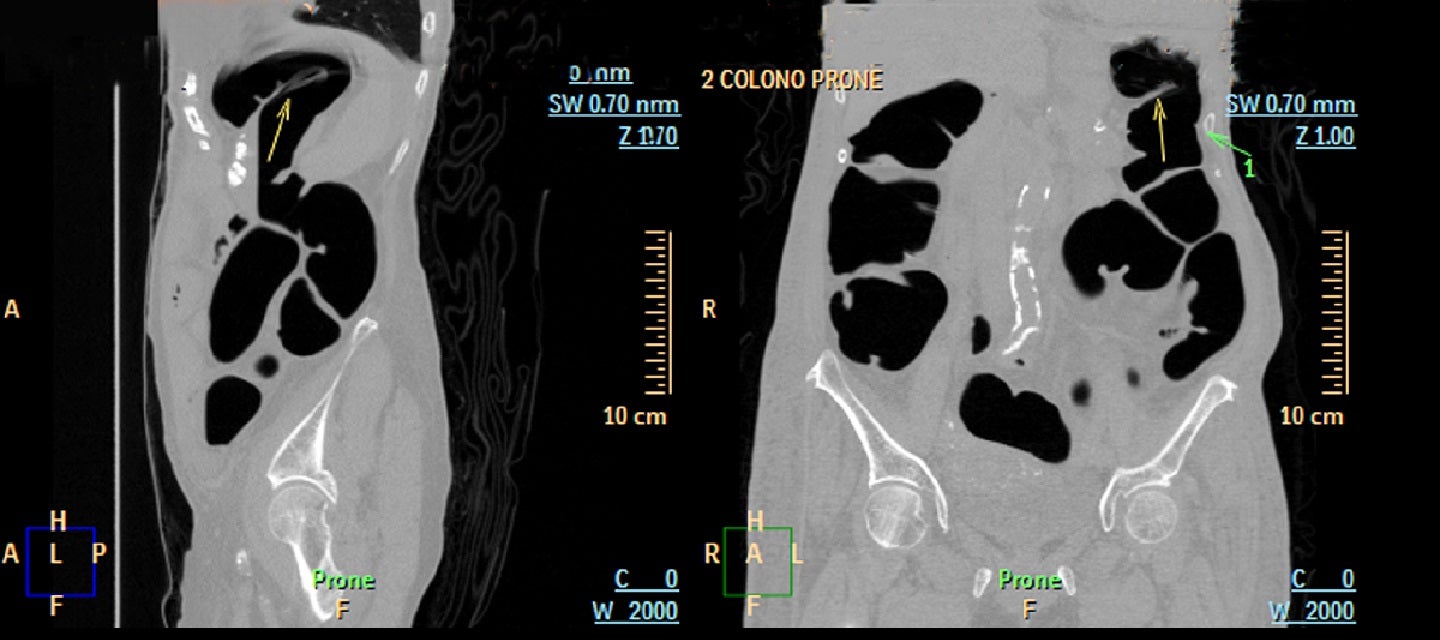

Fearing discomfort due to endoscopy, patients often request an ultrasound instead, but these are not interchangeable. Modern CT machines have a mode that can conditionally be considered a replacement for colonoscopy, it is called “virtual colonography”.

During the study, a 3D model of the large intestine lumen is built using a special program and preparation. However, if the doctor suspects some kind of pathology, it will still be necessary to do a classic colonoscopy.